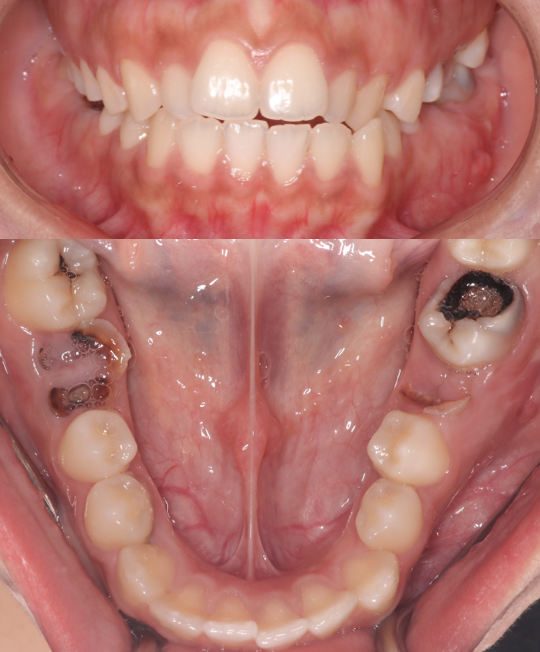

BRACES - SPACE CLOSING

This patient presented with generalized spacing and misaligned teeth. Through comprehensive orthodontic treatment using braces, we successfully closed all spaces and aligned the teeth into an ideal arch form. A fixed lower retainer was placed to maintain long-term stability. The result is a healthier, more confident smile with improved function and aesthetics.